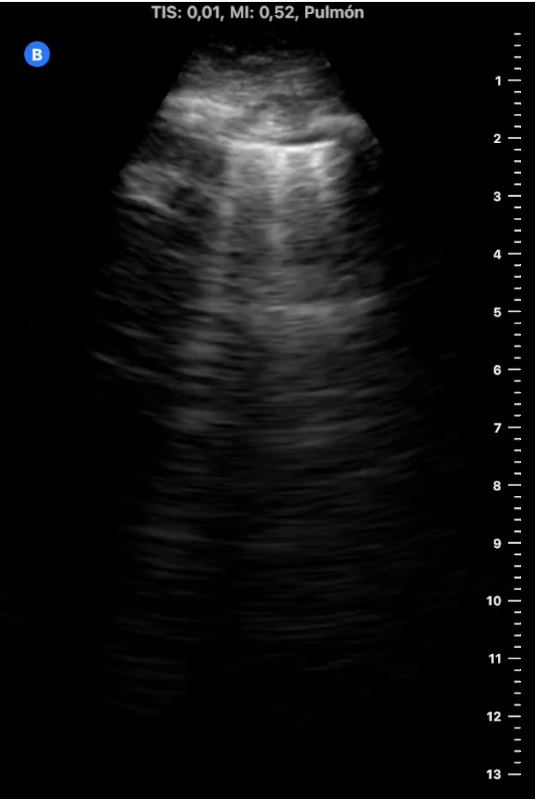

Ecografía pulmonar en AP:

«Líneas B en campos pulmonares izquierdos y consolidación pulmonar en base derecha con mínimo derrame pleural, compatible consolidación infecciosa vs tromboembólica.

Se amplía estudio con ETT que no muestra signos de sobrecarga de ventrículo derecho, y eco Doppler de MMII sin hallazgos de TVP con venas safenas y femorales permeables y colapsables».